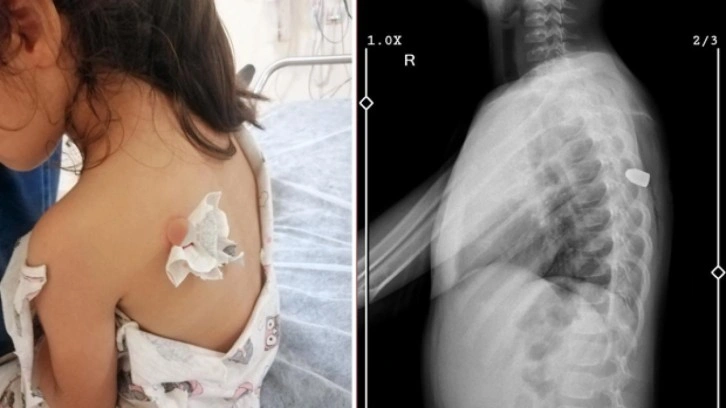

Haberler Asayiş Asayiş Haberleri Denizde akıntıya kapılan kadın 7,5 saat suda yüzerek hayatta kalmayı başardı Davulcu, davul çalarken düğün konvoyundaki kamyonetten düştü Afyonkarahisar'da kahreden olay: 3 ve 13 yaşındaki iki kardeş canından oldu Muavin tartıştığı yolculara plastik çekiçle saldırdı! O anlar kamerada Van'da yürek yakan olay! 2 çocuk girdikleri kuyuda boğuldu Esenyurt’ta 28 yaşındaki gece bekçisi evinde ölü bulundu Giresun’da korkunç olay! Eşini vuran yaşlı adam aynı silahla intihar etti Ameliyatta unutulan gazlı bezle 18 yıl boyunca yaşadı: Yüzde 73 engelli haline geldim Maganda kurşununun yeni kurbanı Meliha! Minik kız sırtından vuruldu Konya'da feci kaza: Karı-kocayı ölüm ayırdı Düzce'de feci kaza: Bariyere saplanan otomobilin sürücüsü öldü! Ardahan'da silahlı kavga: 1 kişi öldü, 1 kişi yaralandı! Muğla'da zincirleme kaza! Ölü ve yaralılar var Mersin'de iki aracın kafa kafaya çarpıştığı kazada 5 kişi yaralandı Hırsız çaldığı televizyonu taşımakta zorlanınca esnaf yardım etti Türkiye'nin en yüksek göllerinden kabul ediliyor! Mahsur kalan 5 kişi kurtarıldı Tunceli'de ayak bileği kırılan kişi için ambulans helikopter kalktı Diyarbakır ve Bingöl'de 16 milyon kök kenevir bitkisi ele geçirildi Gaziantep'te, yasa dışı silah imalatı ve ticaretine 3 tutuklama Alacak tartışmasında öldürüldü Şanlıurfa'da 6 katlı binada yangın «‹112113114115116›»